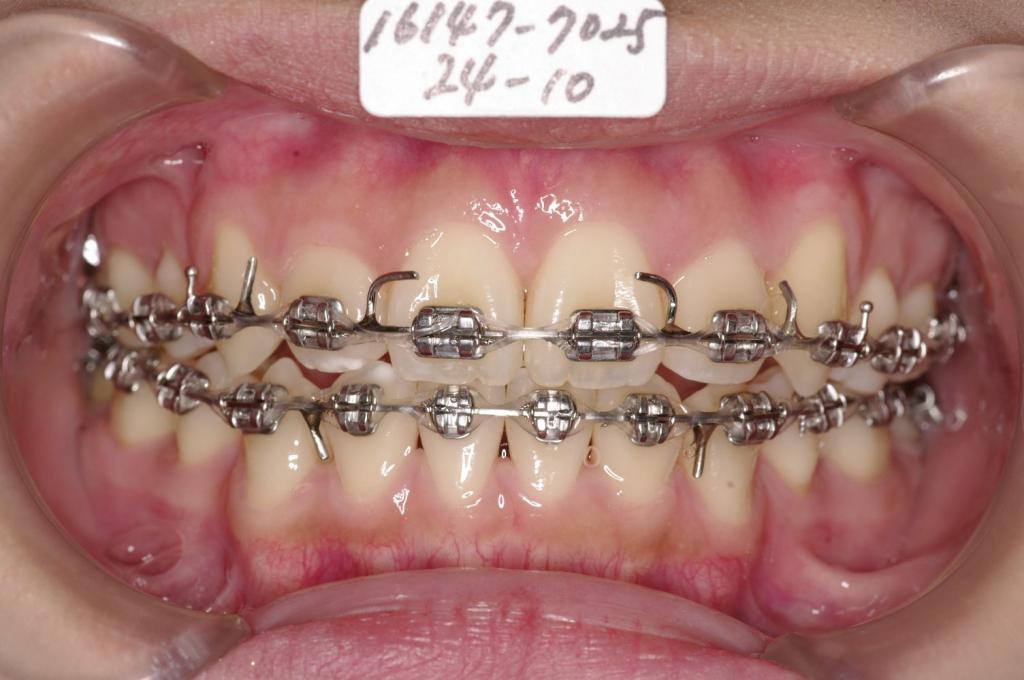

主訴八重歯

装置の種類及び治療法 診断:叢生

治療方法および装置:マルチブラケット装置

High pull J-hook headgear

抜歯:右上4 /左上4

右下4 /左下4

欠損歯:右上8 /左上8

右下8 /左下8

治療期間:14ヶ月

装置写真

治療前

歯並び・咬み合わせ・八重歯・乱杭歯の矯正治療前口内写真NO.1220